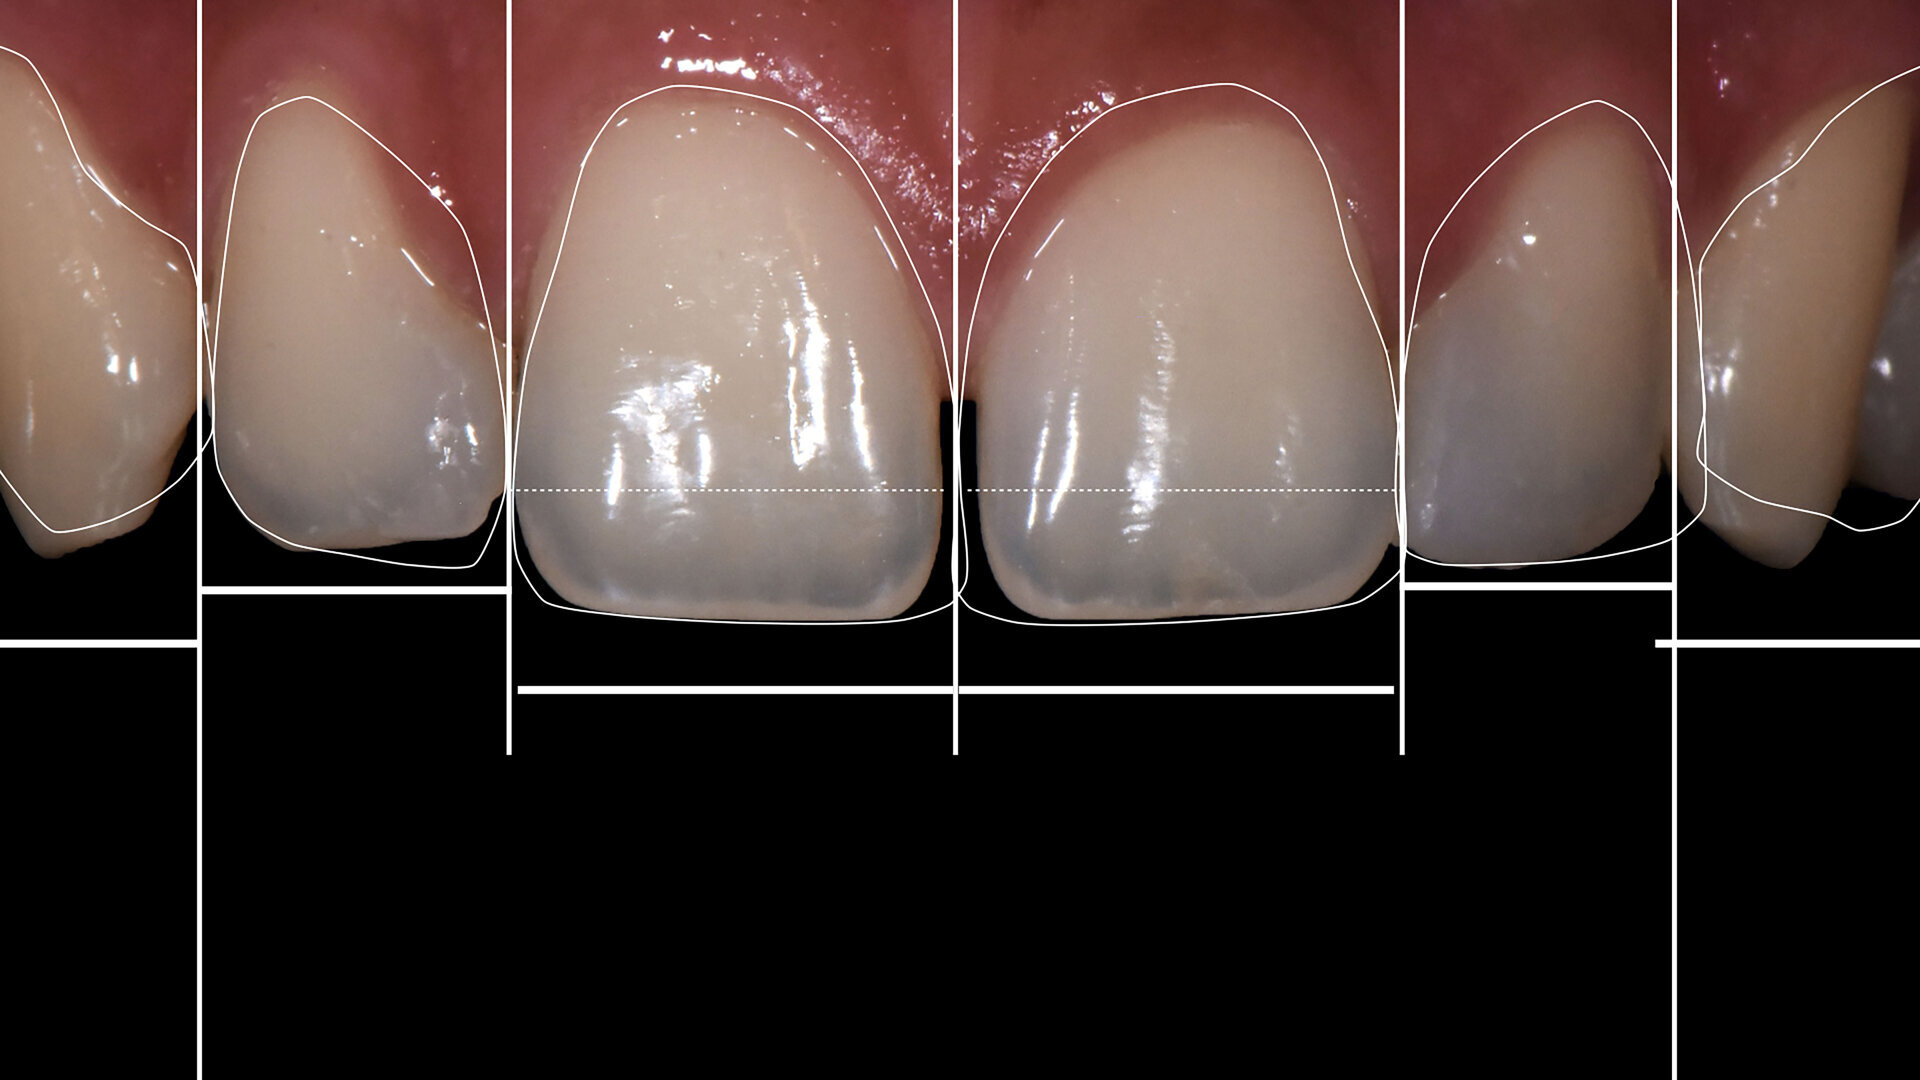

The Digital Smile Design (DSD) visual technology (DSD Planning Center) for a thorough analysis based on the proportions between the teeth was used. The patient was shown the new geometric lines of the planned restorations.

We followed a thorough analysis of the chromatic spectrum, as described by Naorungroj, to accurately and precisely establish the shades to be used in the operative steps (Fig. 2).1 The photographic material was carefully analysed to determine the ideal work planes to gain the information required to achieve the ultimate aesthetic aim of the treatment.

Figs. 2a–d: Choice of shade values.

Fig. 2b

Fig. 2c

Fig. 2d